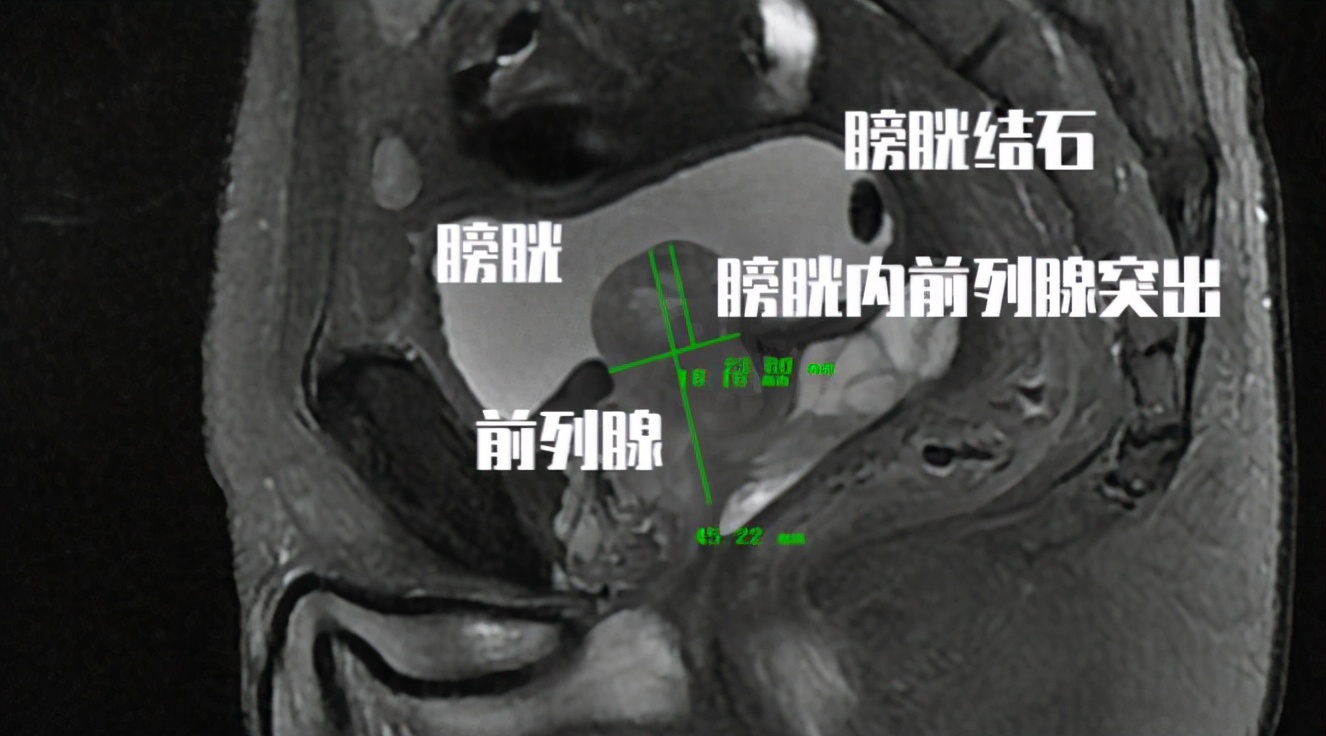

老王今年74岁, 3个月前自诉突发排尿困难,尿线变细来医院就诊 。在当地医院查CT提示 前列腺增生伴膀胱结石,最大膀胱结石体积1.8cm。 粗略估计了一下老王膀胱里的膀胱结石大概不下20颗。老王很奇怪, 为什么他有膀胱结石,而且有这么多结石,但是为什么自己什么感觉都没有呢?

老王的膀胱结石